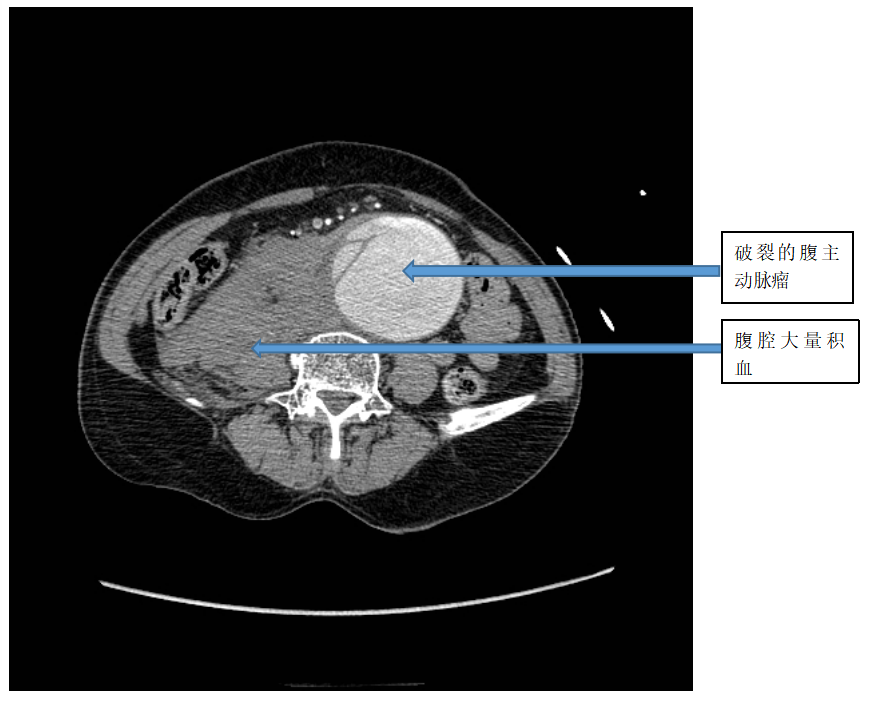

近日一位老年女性患者,因“突发腹痛2小时”入我院急诊科。CT提示腹主动脉破裂,腹腔大量积血。